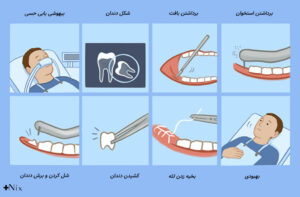

دندانپزشک برای بررسی دقیق وضعیت دندان عقل، دهان شما را معاینه میکند و در صورت نیاز از عکسهای رادیولوژی مانند OPG یا CBCT کمک میگیرد تا زاویه و محل دندان را بسنجد.

اما زمانی که دندانپزشک التهاب، درد یا فشار را در دندانهای دیگر مشاهده کند، درمان دارویی یا جراحی را پیشنهاد میدهد. دندانپزشک با تجویز داروهای ضدالتهاب و آنتیبیوتیک، عفونت را کنترل میکند و درد را کاهش میدهد.

اگر دندان عقل باعث درد، التهاب یا عفونت شود، دندانپزشک آن را با بیحسی موضعی خارج میکند.

بعد از جراحی باید استراحت کنید و طبق دستور پزشک از داروهای مسکن استفاده کنید.

برای کاهش تورم، کمپرس یخ روی صورت بگذارید و از غذاهای نرم مانند سوپ یا پوره سیبزمینی استفاده کنید.